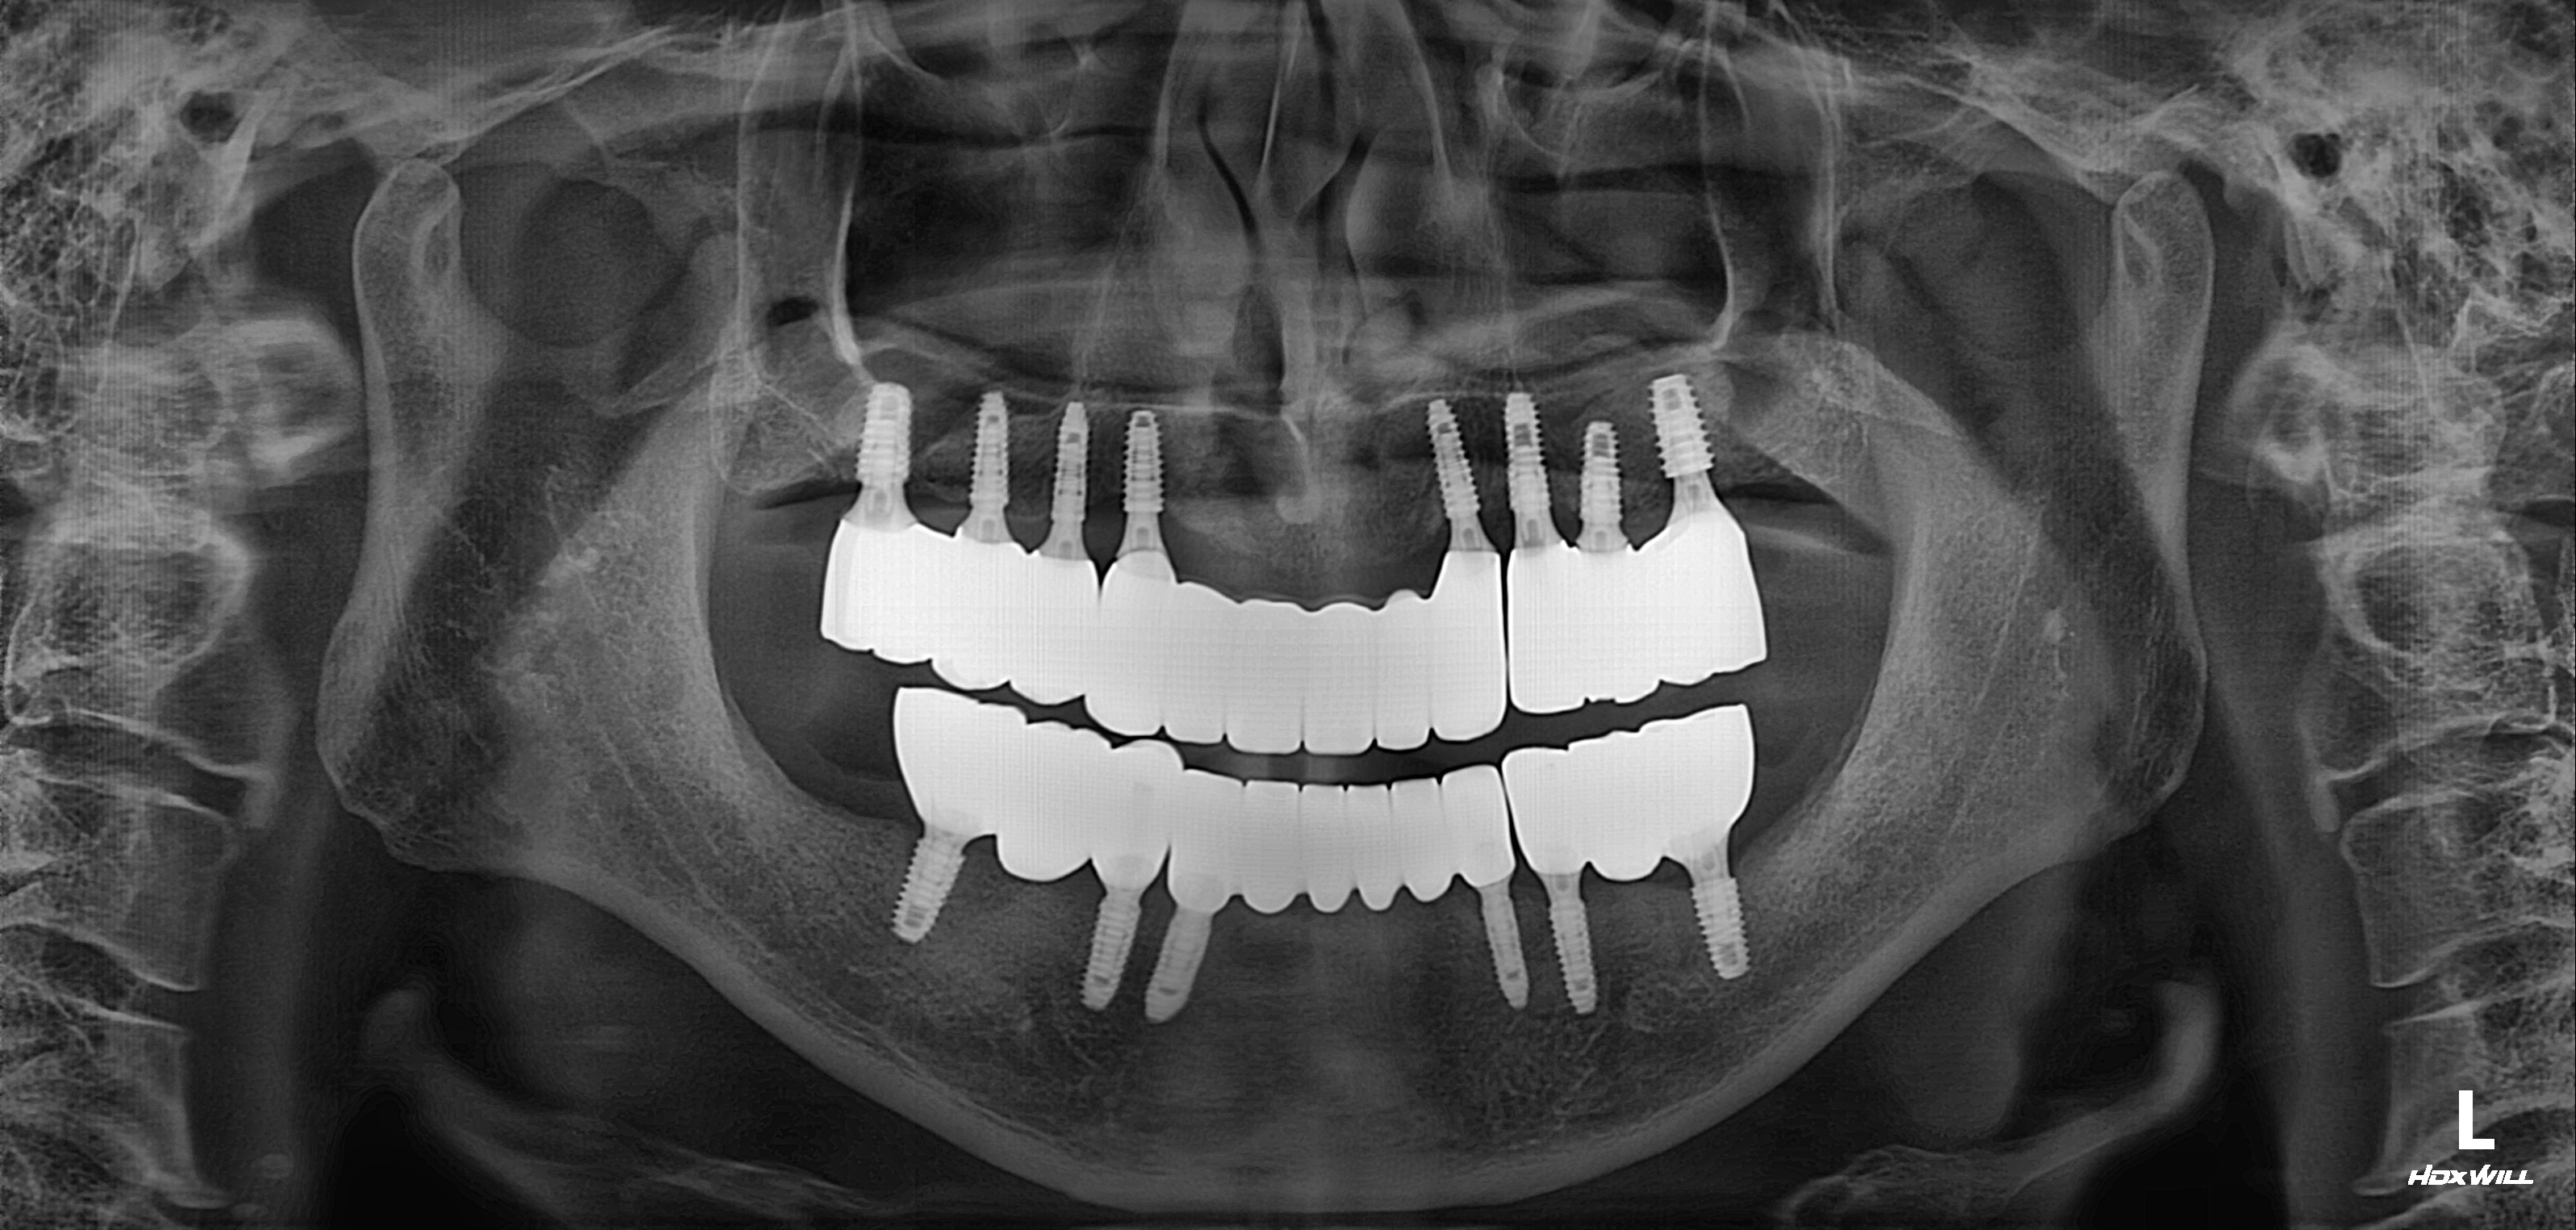

수술 전

수술 후

전악임플란트 식립사례

전후사진